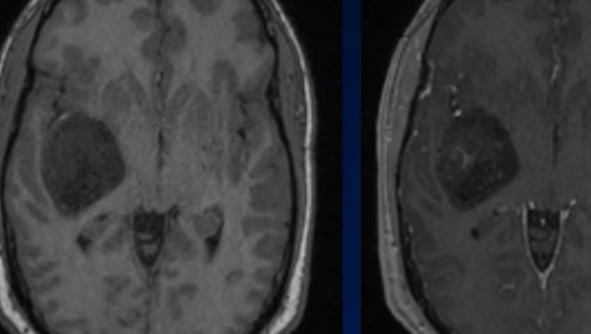

Glioblastome

Decouverte fortuite aux urgences, Confirmé a la patho

Decouverte fortuite aux urgences, Confirmé a la patho

Glioblastome (grade IV)

- Peu de chance de survie (15mois médian)

- Oedème (mélange entre infiltration + oedème vasogénique)

- Meilleur signe pour la récidive = La prise de contraste

- Nécrose centrale

- Hémorragies

- TTT: résection maximale + Radiation du lit opératoire

- Post traitement radiothérapie → augmentation des plages périphériques T2

- Primaire vs Secondaire (Dégénérescence d’un gliome de bas grade)

Agressive, mal délimitée